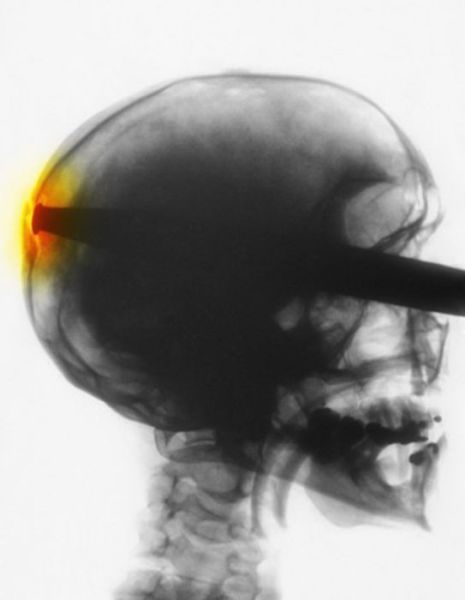

Я, конечно, не специалист, но по-моему, тут не нужен был рентген, чтобы понять, что произошло

Это… больно!